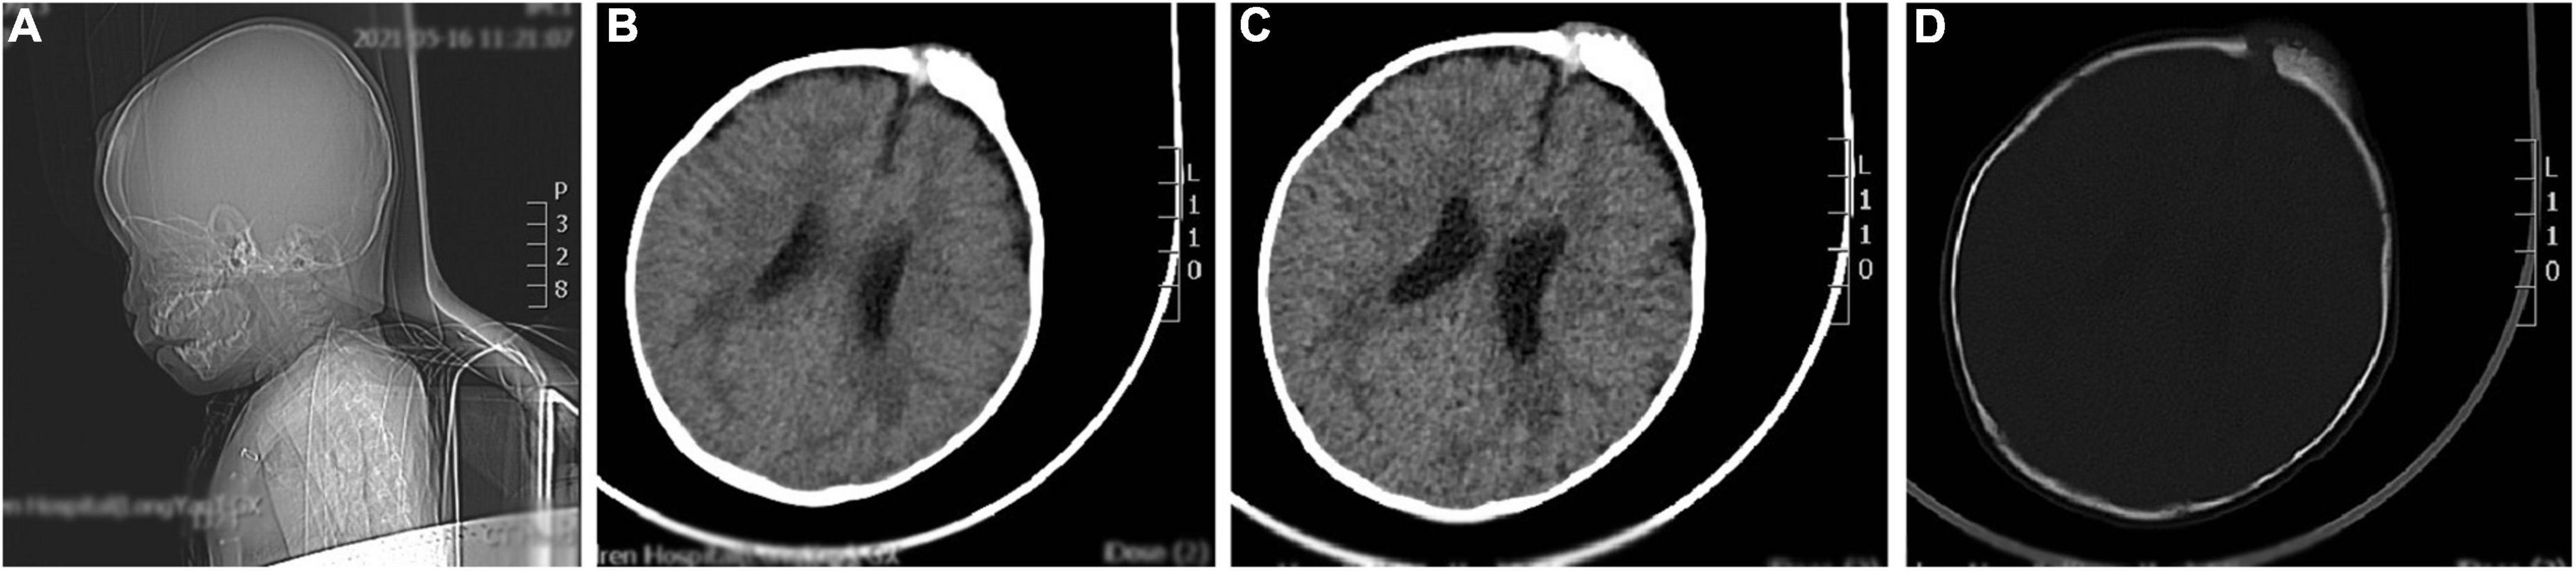

Brain computed tomography scan details

The brain CT scan showed irregular bone structure with mixed density mass on the left side of the cranial plate in the forehead, slightly reduced brain mass density in the bilateral parietal lobes, and wider ventricles and extracerebral spaces as shown in Figure 1.

Figure 1. A representative image of the head CT scan shows the irregular bone structure with mixed density mass on the left side of the cranial plate in the median frontal area, slightly reduced density in the bilateral parietal lobes, widening of the ventricles and extracerebral space, and thickening of the septal sinus mucosa. (A) Sagittal view shows a mass in the frontal area. (B,C) Soft tissue window at the central level of the lateral ventricle show a high-density mass in the left frontal region. (D) Bone window at the central level of the lateral ventricle: the bony structure of the left cranial plate in the middle frontal region is irregular, and there is a mixed density mass shadow.